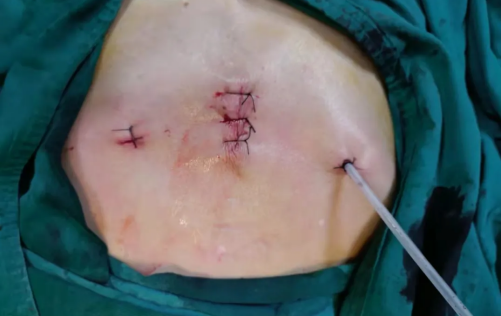

手术仅用时仅两小时,术中几乎无出血,术后第一天即可下床活动,第二天就拔管出院。你能想象这是一例胸腺瘤患者的肿瘤切除手术吗?

来自渔溪镇的万大爷,因此前无明显诱因出现胸闷、胸痛,且呼吸时疼痛加重,遂到恩阳区人民医院门诊就医。CT检查提示“纵膈占位”,随即收入胸外科(外一科)住院治疗。科主任陈旭在组织胸外科团队进行充分讨论分析后,拟行难度更大、创伤更小的“经剑突下入路胸腔镜纵膈肿瘤切除术”为患者治疗,并于近期成功实施该手术。 经剑突下入路胸腔镜纵膈肿瘤切除术相较于传统纵膈肿瘤切除术而言,具有术后伤口美观、疼痛减轻、暴露充分、标本易取出等优点。并且能彻底避免手术对肋间神经和肌肉等胸壁组织损伤,较好保持胸壁完整性,降低术后对呼吸功能的影响,缩短了胸管留置体内的时间和患者住院时间,有利于患者快速康复。

该例手术的成功实施,标志着恩阳区人民医院在微创技术领域又有了新的突破。长期以来,恩阳区人民医院始终坚持以患者为中心,致力于钻研新技术、开展新业务,更好地应用于临床,让群众患者享受到“大病不出县”的便捷和更高质量的医疗服务。